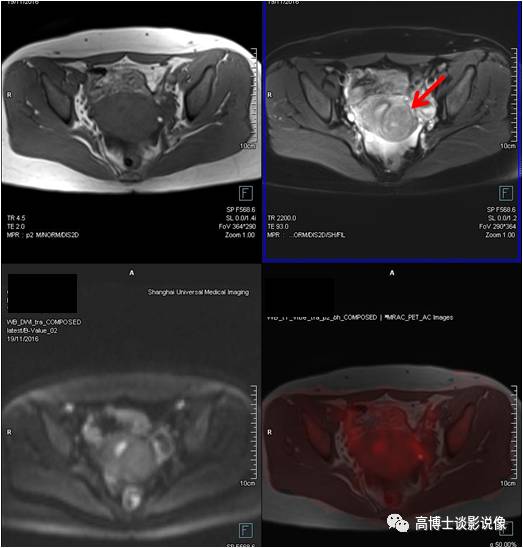

子宫肌瘤

年轻女性,无明显不适。子宫后壁肌层可见一椭圆形异常信号灶,长径约3.3cm, FDG无代谢,诊断为子宫肌瘤。

点评

子宫肌瘤是女性生殖系统中最常见的一种良性肿瘤。子宫肌瘤较小或者不位于黏膜下的,一般无症状,明显增大后会压迫膀胱等邻近脏器,或者造成月经量增多,甚至腹痛等不适。常规检查B超可以解决问题,PET/MR可以帮助鉴别子宫病变良恶性。治疗因人而异。

卵巢囊肿

年轻女性,无明显不适。左侧附件区见一长径约5.0cm椭圆形囊性信号灶,边界清楚,FDG未见明显摄取,考虑为卵巢囊肿。

PET/MR检查常常会发现卵巢囊性病变,多数为生理性囊肿(滤泡或黄体囊肿),均与女性内分泌功能相关,随着体内激素水平的变化而变化,因此发现此种卵巢囊肿后不必过分紧张,大于3cm者,建议B超定期随访复查。